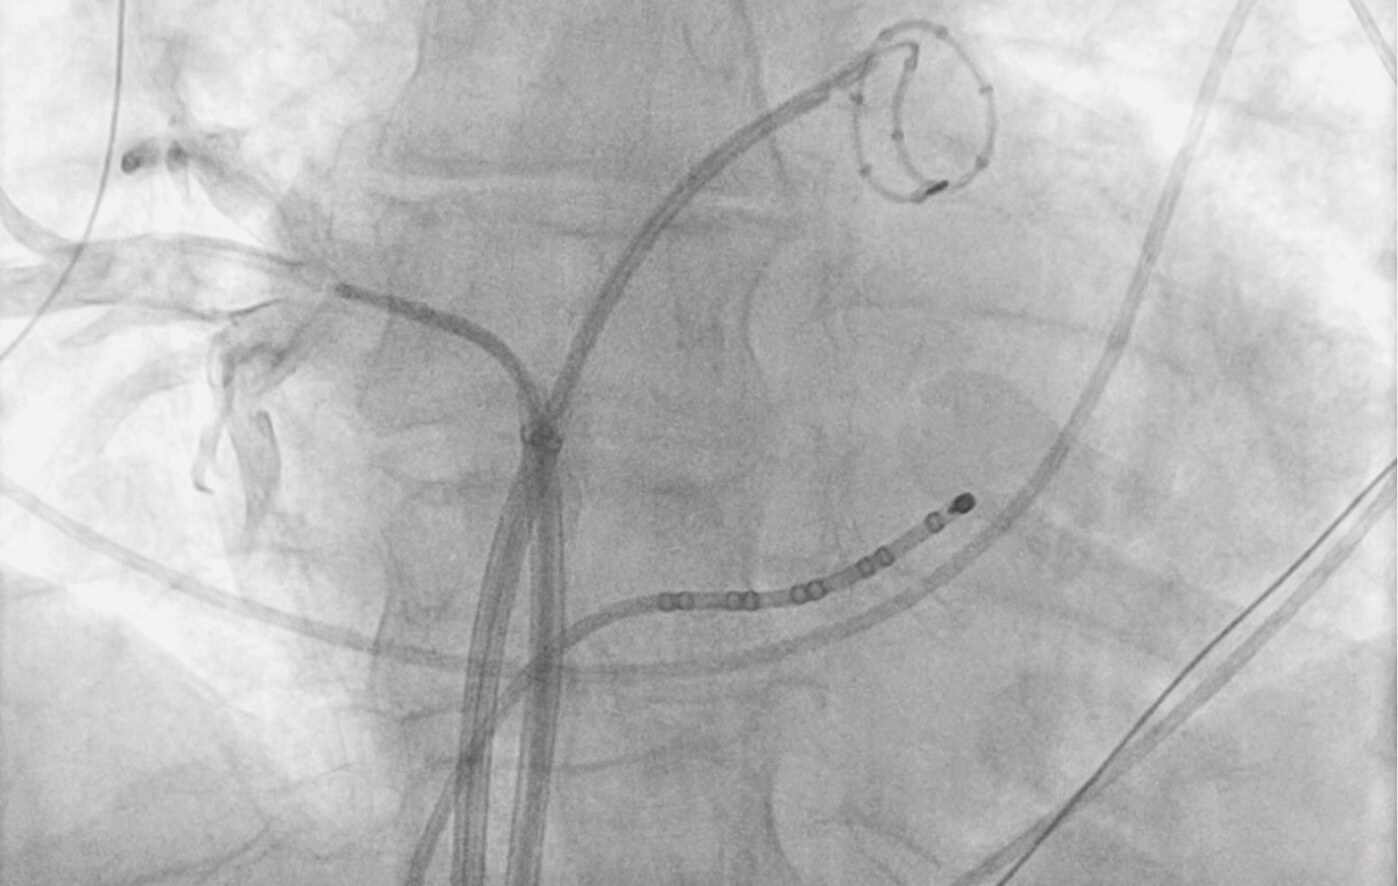

Die elektrophysiologische Untersuchung (EPU) dient der genauen Analyse von Herzrhythmusstörungen. Dabei werden über die Leistenvenen Katheter in das Herz eingeführt, über die elektrische Impulse gemessen und analysiert werden können.

So lassen sich Ursprungsorte von Herzrhythmusstörungen gezielt identifizieren. In gleicher Sitzung kann bei Bedarf eine Ablation (Ver- ödung) durchgeführt werden, um die Rhythmusstörung dauerhaft zu beseitigen. Mit Hilfe moderner 3D-Mappingverfahren ist es uns möglich, alle komplexen Herzrhythmusstörungen darzustellen und zu behandeln.

Eine der am häufigsten auftretenden Herzrhythmusstörungen ist das Vorhofflimmern. Die effektivste Methode zur Verhinderung von Vor- hofflimmern ist die kathetergeführte Pulmonalvenenisolation (Abla- tion) der Eingänge der Lungenvenen im linken Vorhof. Wir wenden hierbei die schonende und sehr sichere Methode der Cryoablation („Kälteballon“) an.